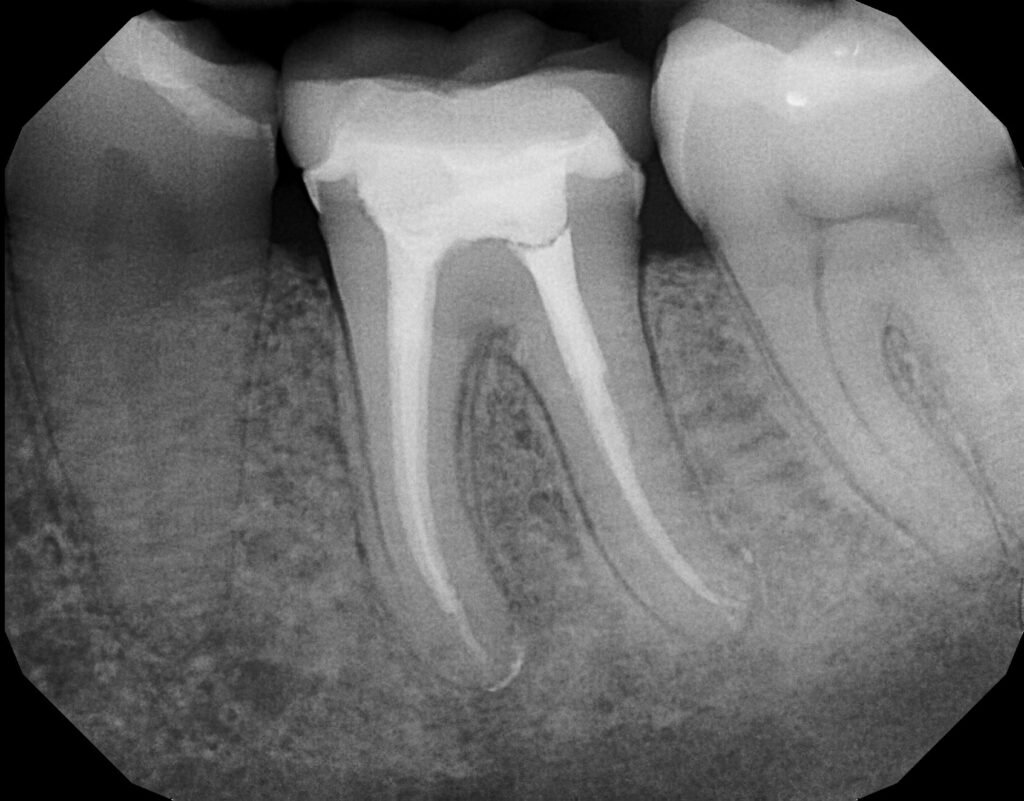

4.2. Les Instruments de Préparation Canalaire

4.2.1. Instruments de Cathétérisme Canalaire

- MMC (Micro Méga Cathéter)

- Lime K

4.2.2. Instruments de Préparation Canalaire Proprement Dite

La Lime K (Kerr)

- Symbole d’identification: Carré.

- Spirales: 1.5 à 2.5 spires par mm, avec un angle d’hélice moyen de 40°.

- Action: Limage (mouvement de va-et-vient).